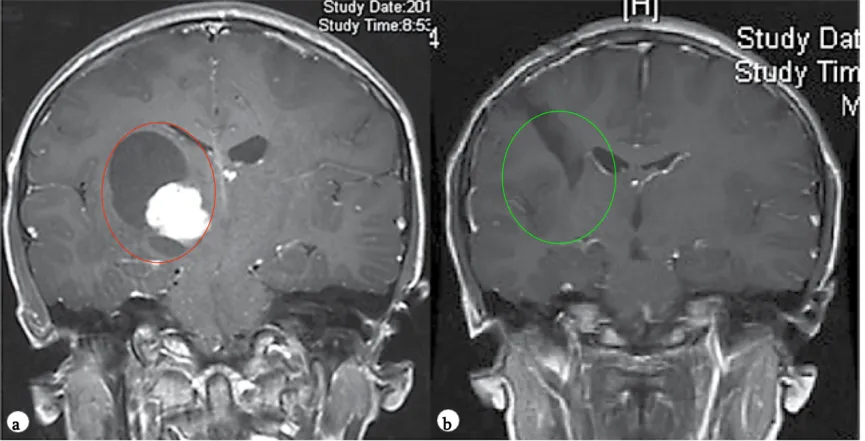

毛细胞星形细胞瘤是儿童年龄组中常见的神经胶质瘤亚型,主要发生于幼儿(中位年龄为4岁)。PA在后颅窝、视神经通路、背侧外生性脑干肿瘤中占比较大,在T1加权磁共振成像上通常表现为低信号的囊性肿块,其强化部分显示明亮增强(见图1)。

图1:患儿术前(a)与术后(b)颅脑磁共振成像对比。术前影像显示右侧丘脑区域存在巨大囊实性占位,提示胶质瘤可能,可见皮质脊髓束(负责人体肢体运动的神经传导束)受压及脑室扩大。术后影像证实肿瘤已实现全切,脑组织复位良好,未见脑出血、脑水肿等手术损伤征象。